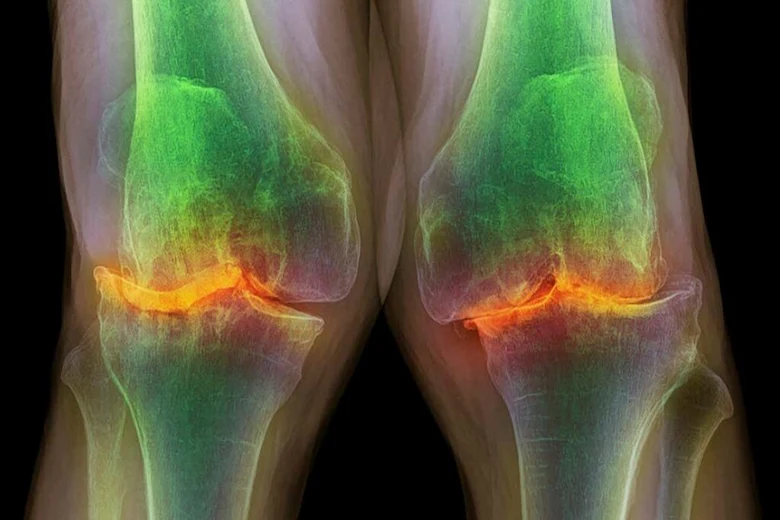

تورم و التهاب در ناحیه زانو

اما تورم مفصل یکی دیگر از نشانههای بارز آرتروز زانو است که ممکن است به صورت تجمع مایع، التهاب بافتها یا احساس گرمی و قرمزی در اطراف مفصل بروز کند. این تورم معمولا پس از فعالیتهای طولانی مدت یا فشار زیاد بر زانو تشدید میشود و گاهی با درد ضربان دار همراه است. تورمهای مکرر نشان دهنده فعال بودن التهاب در مفصل و تخریب تدریجی ساختارهای داخلی زانو هستند که در صورت عدم درمان میتوانند روند بیماری را سرعت دهند.